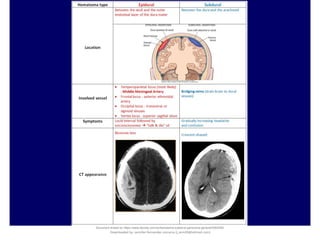

Acute SDH is readily visualized on head CT as a high-density crescentic collection across the

hemispheric convexity

Subacute and chronic SDH appear as isodense or hypodense crescent-shaped lesions

that deform the surface of the brain

In contrast to SDH, epidural blood produces a convex pattern on CT because its collection is

limited by firm dural attachments at the cranial sutures